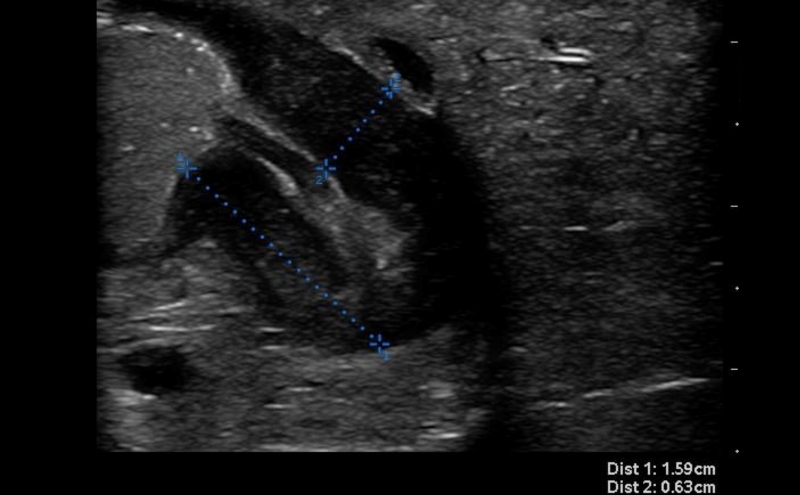

- Thickness of the pyloric muscle can be measured in the long or short axis view

- Figure 6. Hypertrophied pyloric muscle in long axis measuring 4.3mm

- A thickness of ³3mm is considered abnormal or hypertrophied